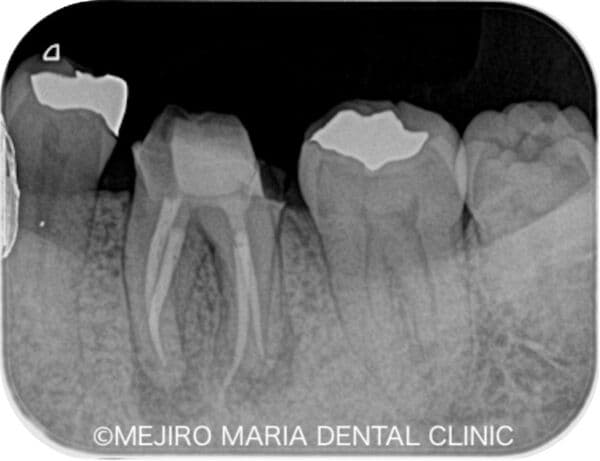

無症状で進行する虫歯・原因不明の歯肉の腫れを、コンセプトを守った初回根管治療(精密根管治療)で治癒

歯髄壊死の症例

| 主訴 | 左下奥から2番目の歯(下顎第二大臼歯)が年に数回腫れることがある |

|---|---|

| 治療内容 | 根管治療(抜髄)|精密根管治療 |

| 治療期間 | 1週間 |

| 治療費用 | 181,500円(税込)※支台築造処置を含む |

| リスク・副作用 | ・治療計画は口腔内、歯牙の状況により変更する場合があります。 ・下顎に対するインプラントを含む外科的処置にて下歯槽神経を損傷した場合、顔面に知覚麻痺が生じる場合があります。 ・当院の補綴処置の保証期間は5年間ですが、3ヶ月〜6ヶ月の定期的なメインテナンス、定期検診に来院されていない場合は適用されません。 |